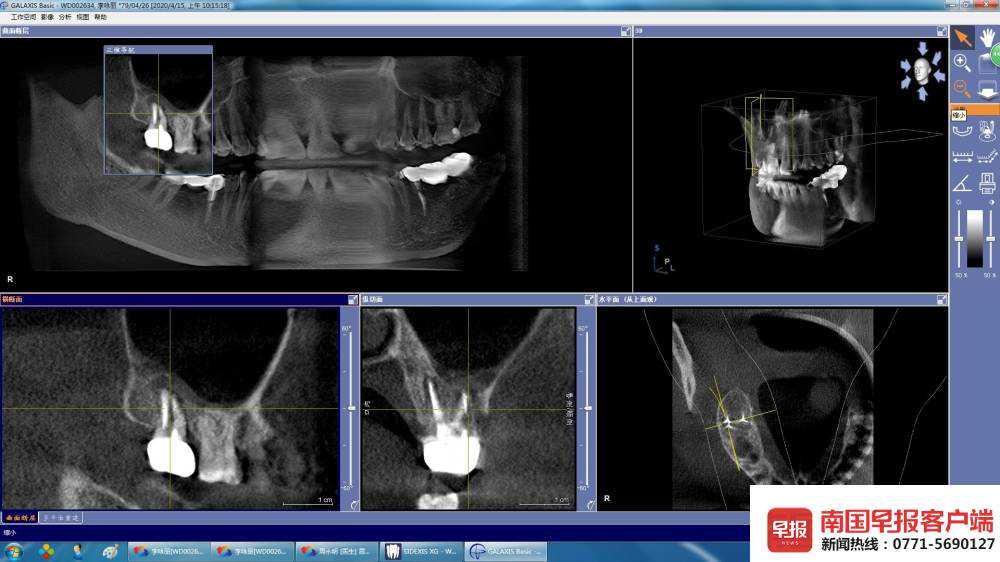

近日,南宁市民李女士向南国早报客户端记者反映称,2016年9月份,她在南宁天使口腔医院(下称天使口腔)做了牙冠之后一直发炎。今年4月20日,广西医科大学口腔医院诊断为慢性根尖周炎、慢性牙周炎,需拆除冠部修复体,之后再做根管治疗。

拍片显示的牙冠(白色)。

李女士认为是天使口腔为她做牙冠炎症未消,导致骨头慢慢坏死。5月1日,天使口腔回应称,他们的诊疗过程中都是规范的,双方纠纷可以依法进行医疗鉴定。5月5日,南国法援公益律师认为,解决这个问题,当事双方须进行协商,确定一家鉴定机构进行鉴定,如果双方协商不了,可由法院来确定鉴定机构进行鉴定。

4月20日,广西医科大学附属口腔医院牙体牙髓科诊断为“慢性根尖周炎、慢性牙周炎”,治疗计划为方案一:根尖手术;方案二:拆除冠部修复后行根管再治疗。“后续治疗非常麻烦,不但要手术,还要植骨,况且费用也很高。”

拍片显示的牙冠。